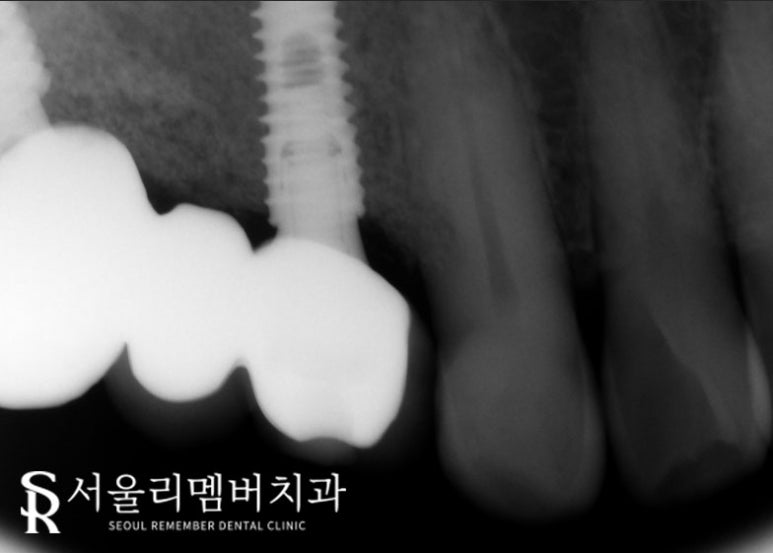

전치부에만 국한된 문제가 아닌,

전체 치아에서 관찰되고 있었는데요.

특히 임플란트를 올려놨던 치아 주변에서 심하게 나타났습니다.

치주 질환이 진행되어 치은이 밑으로 꺼지게 된 거죠.